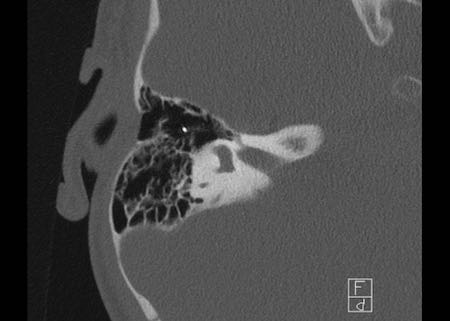

Bên trái là hình ảnh của một bé gái 2 tuổi.

Các hình ảnh từ kết quả chụp CT được thực hiện trước khi cấy ốc tai điện tử.

Quan sát thấy dị dạng nhẹ ở đỉnh ốc tai – không có sự phân tách giữa vòng thứ hai và vòng thứ ba, và trụ ốc tai xương vắng mặt.

Cống tiền đình bình thường.